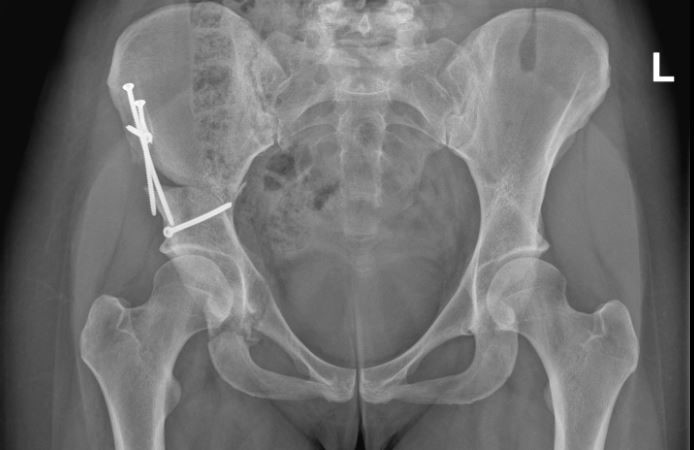

Periacetabuläre Beckenosteotomie

Die periacetabuläre Beckenosteotomie oder periacetabuläre Osteotomie (PAO) ist eine Operation zur Korrektur der Hüftpfannenposition, z. B. im Falle einer Hüftdysplasie und begleitender Hüftarthrose. Der Eingriff erfolgt durch einen einzigen 10 bis 15 cm langen Hautschnitt in der Leiste und dauert etwa 1 bis 2 Stunden. Dabei wird die Hüftpfanne aus dem Becken herausgeschnitten, neu ausgerichtet und in der gewünschten Position fixiert. Anders als z. B. bei der älteren «Triple Osteotomie» bleibt bei der PAO das Becken auch unmittelbar nach dem Eingriff stabil, was eine zuverlässigere Knochenheilung mit schnellerer Mobilisation und Nachbehandlung ermöglicht. Der Geburtskanal der Patientinnen bleibt dabei unverändert, sodass normales Gebären weiter möglich ist.

Bild: Universitätsklinik Balgrist

Korrektur der Pfannenposition

Die periacetabluäre Beckenosteotomie wird durchgeführt, um das Hüftgelenk mechanisch zu verbessern. Dem Problem zugrunde liegt meist eine Hüftdysplasie.